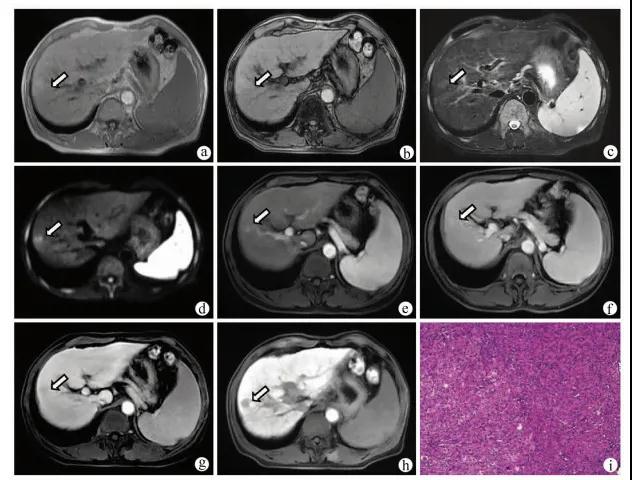

图2 患者男,46岁,HBV感染者,肝硬化合并eHCC注:a,同相位MR T1WI示肝脏S8段等或稍低信号(箭头);b,病灶反相位信号减低,提示其内存在脂肪变性(箭头);c,T2WI呈稍高信号;d,DWI呈稍高信号;e,增强扫描动脉晚期呈等信号(箭头);f、g,门静脉期及延迟期呈低信号(箭);h,肝胆期呈低信号;i,病理学诊断为高分化HCC,其内存在较多脂肪(HE染色,×100)。

图3 患者男,57岁,肝硬化12年,肝脏S6段结节注:a,病灶同相位呈稍高信号(箭头);b,反相位未见信号减低(箭头);c,T2WI呈稍高信号(箭头);d,DWI呈高信号(箭头);e,增强扫描动脉晚期轻度强化(箭头);f,门静脉期呈稍高信号,持续强化(箭头);g,延迟期强化减低,呈低信号(箭头);h,肝胆期呈低信号;i,病理学诊断为高分化HCC(HE染色,×100)。